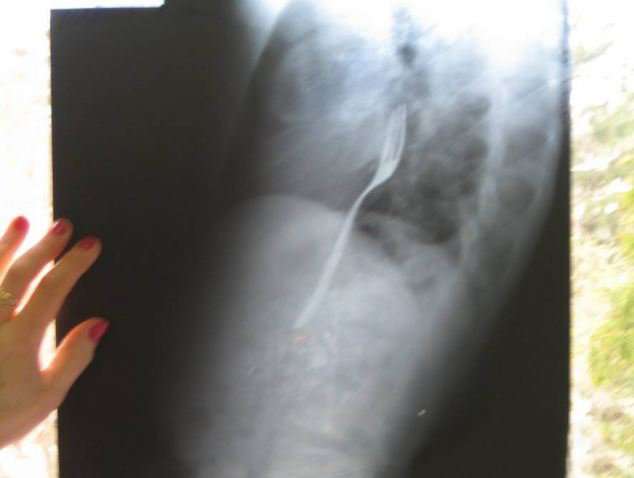

Պարզվել է, որ ռենտգենյան լուսանկարում երևացել է տղամարդու կերակրափողում գտնվող մետաղական պատառաքաղը: